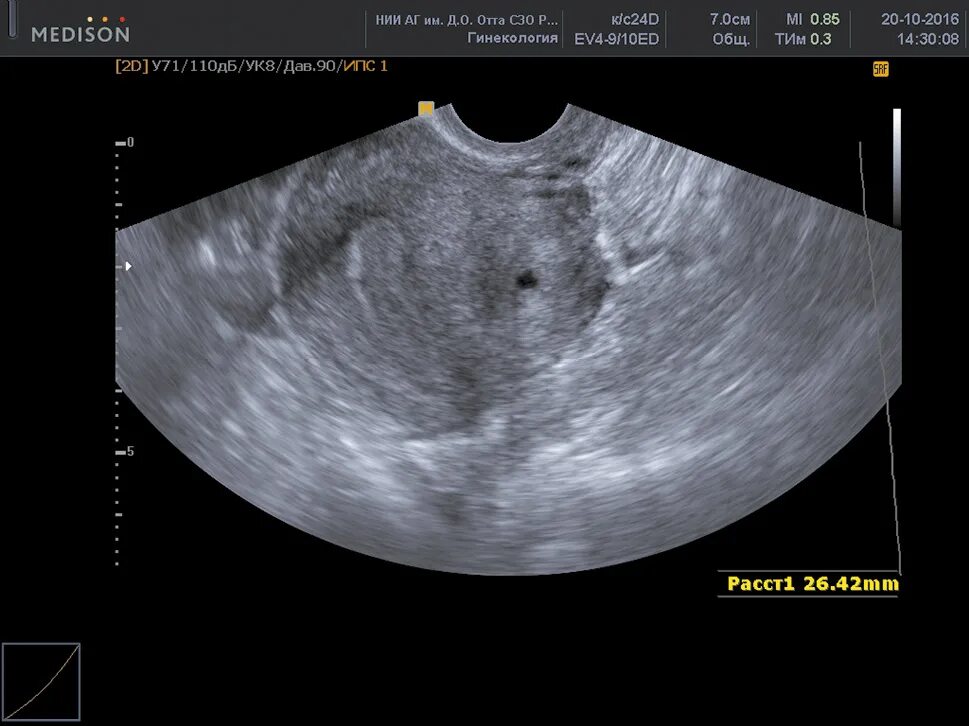

Аденомиоз диффузные изменения